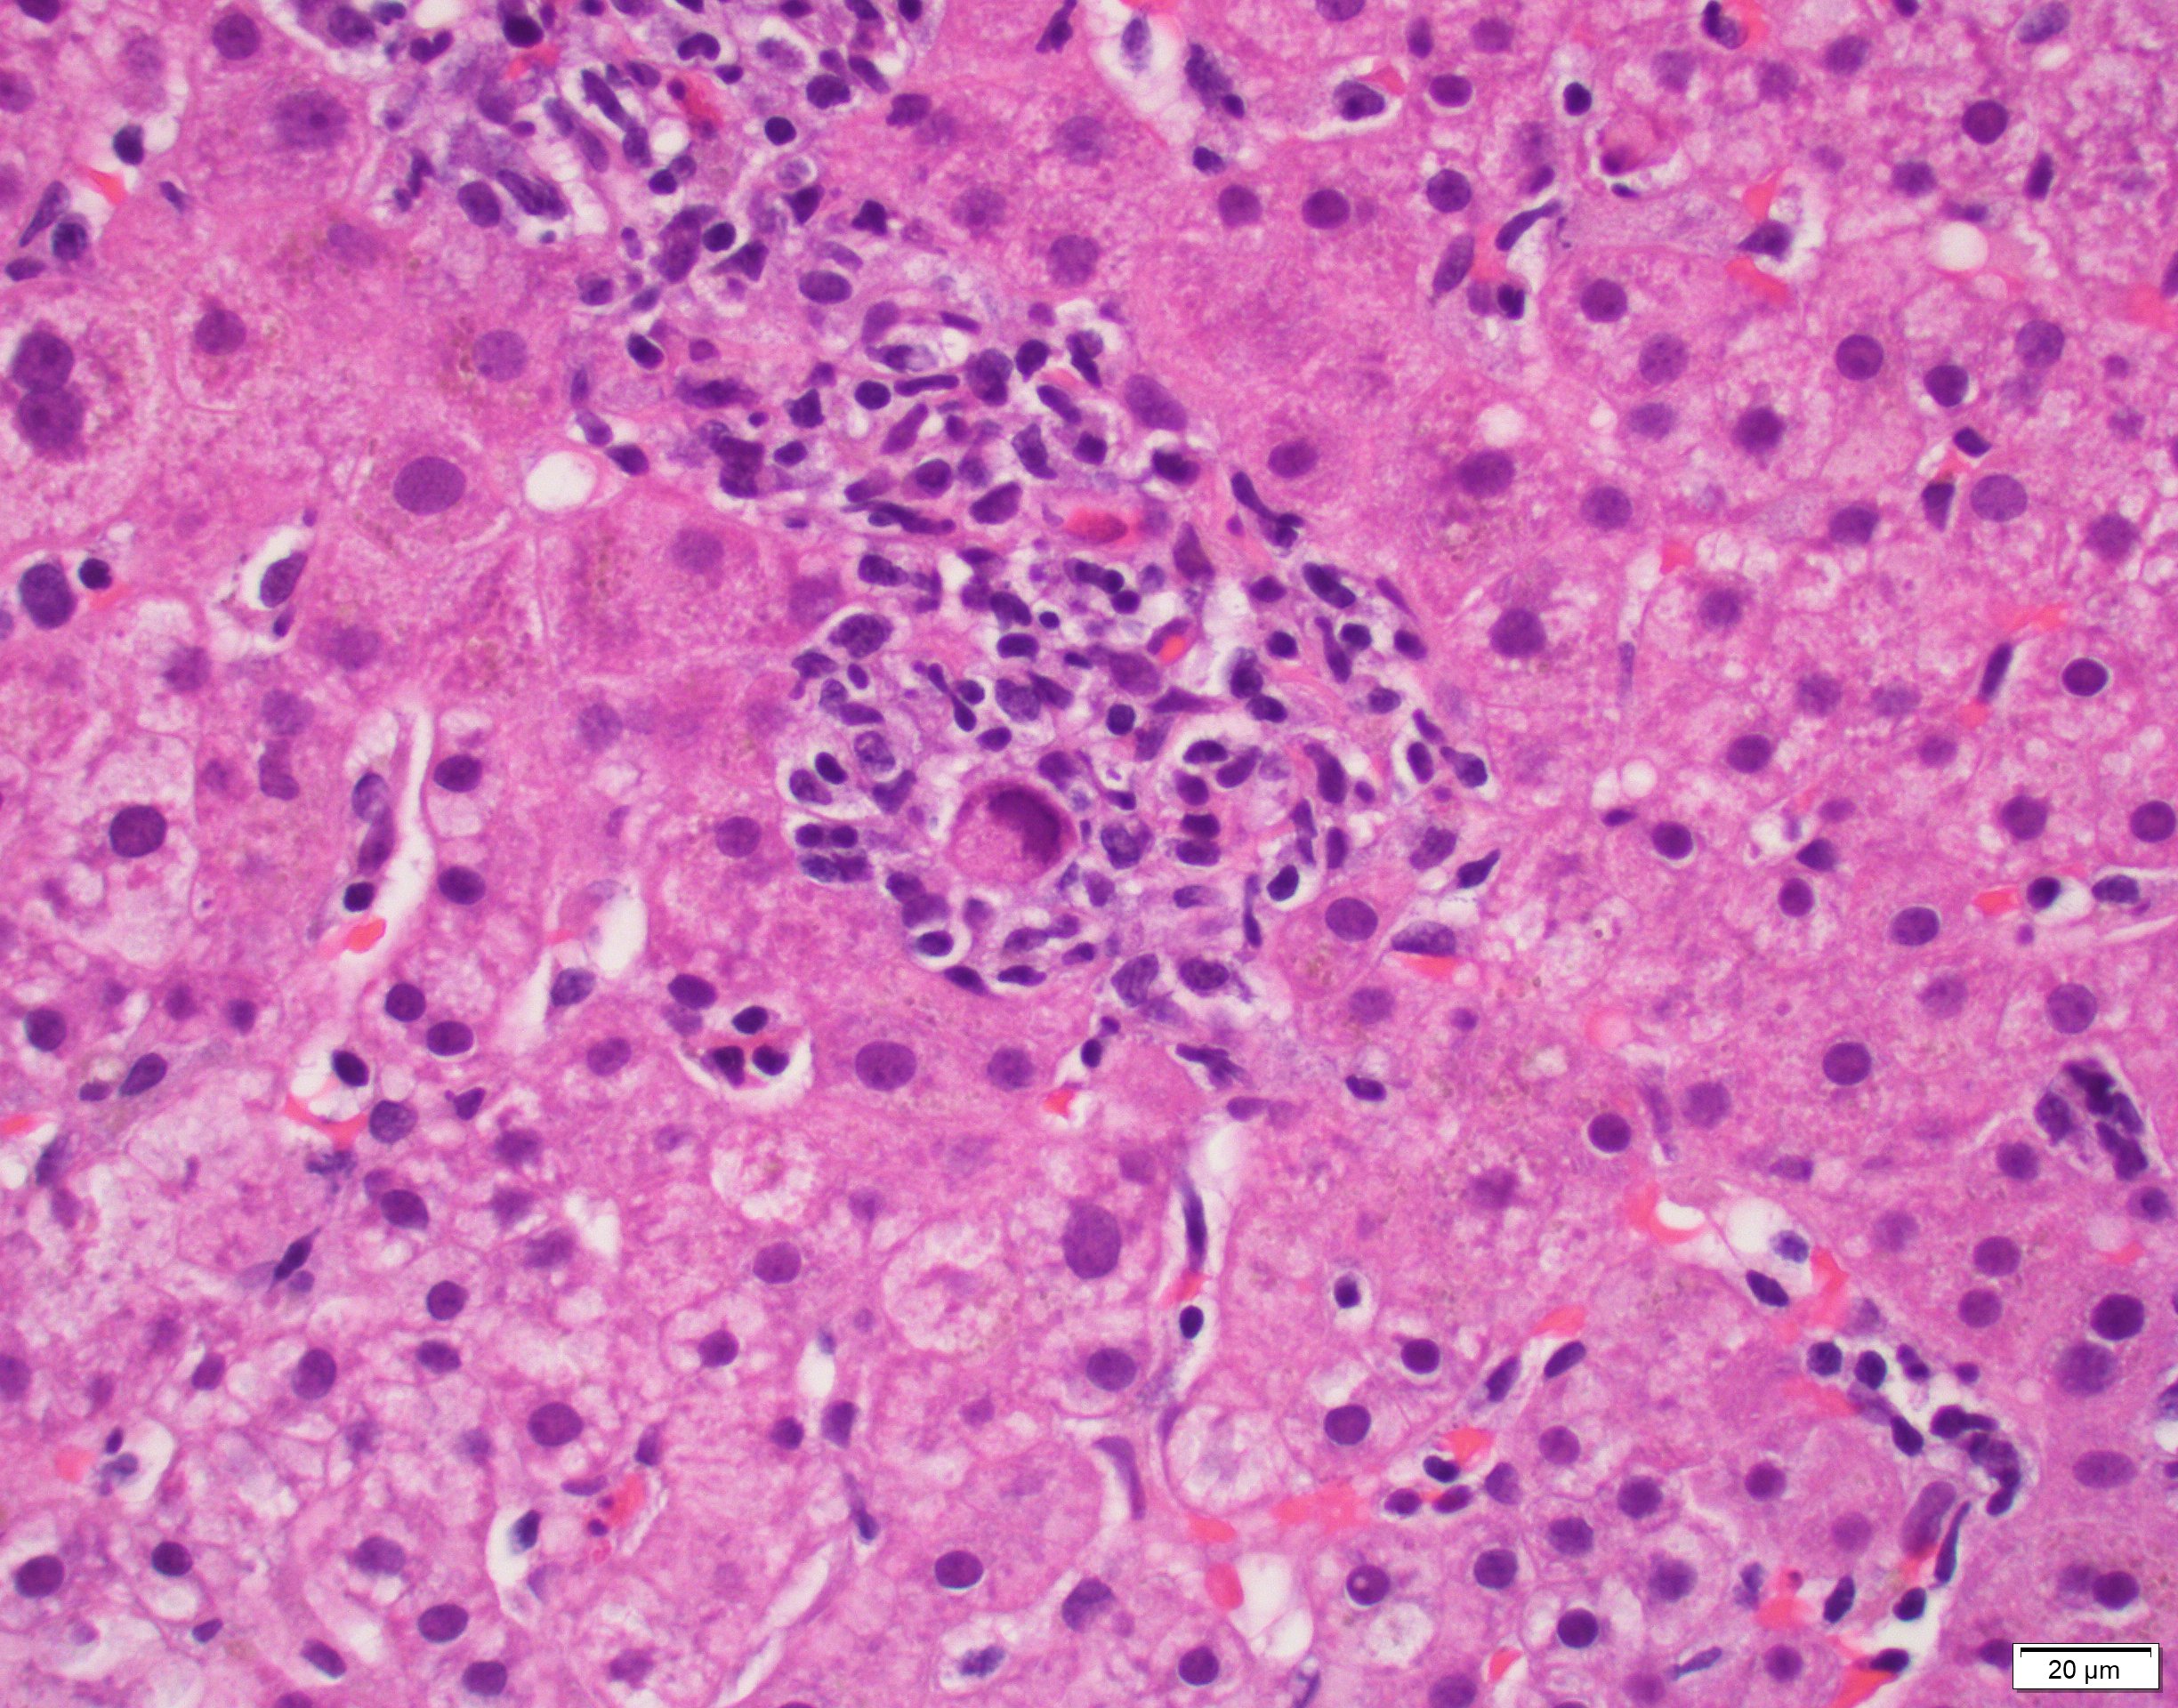

Liver biopsy in chronic hepatitis C. Interface hepatitis, with the Hepatitis C Liver Pathology Outlines Hepatitis b, hepatitis c and hepatitis d virus; Highlights the pathophysiology, microscopic findings and associated hepatic diseases with common structural changes, patterns of cell damage and necrosis, intracellular. • portal, interface and lobular hepatitis • progressive. Chronic viral hepatitis is commonly caused by 3 viruses: The terminology for assessment of chronic viral hepatitis in liver biopsy specimens has become confusing. Hepatitis C Liver Pathology Outlines.